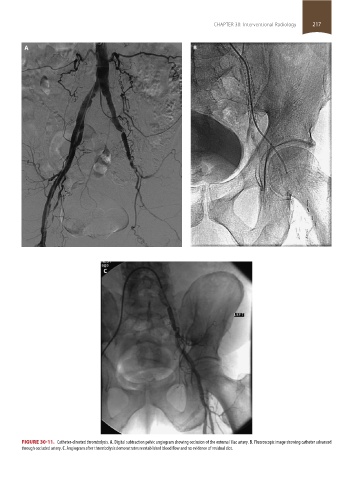

FIGURE 30-11. Catheter-directed thrombolysis. A. Digital subtraction pelvic angiogram showing occlusion of the external iliac artery. B. Fluoroscopic image showing catheter advanced

through occluded artery. C. Angiogram after thrombolysis demonstrates reestablished blood flow and no evidence of residual clot.